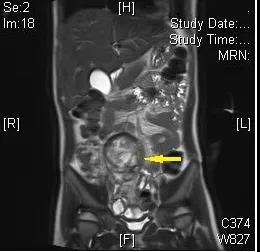

一名4岁的患儿小金(化名),神经母细胞瘤长在盆腔里。据接诊医生林珊主治医师介绍,肿瘤深深的藏在孩子的后腹膜,局部侵犯双侧输尿管,肿瘤还紧紧包绕着肠系膜下动脉、腹主动脉主要分支左右髂动脉和下腔静脉,这些大血管是控制人体血管“主干道”,手术中一旦操作不慎造成损伤,就可能造成大出血、休克、呼吸心跳骤停等严重后果。

▲神经母细胞瘤长在盆腔(箭头所示)

经过多次病例讨论,徐迪教授带领团队决定利用达芬奇手术机器人开展“骨骼化”手术,即借助手术机器人高清放大的3D视野、稳定灵活的操控解剖,将被肿瘤包裹的血管和神经,一根根从肿瘤中剥离出来,以保留这些血管神经功能,实现对肿瘤的“骨骼化”精准切除,之后清扫可疑淋巴结、降低复发风险。整个手术难度犹如“走钢丝”,并需要如庖丁解牛般的解剖技术,好在有惊无险,肿瘤直径约6厘米的肿瘤被完整切除,小金术中几乎没有出血,术后恢复良好。